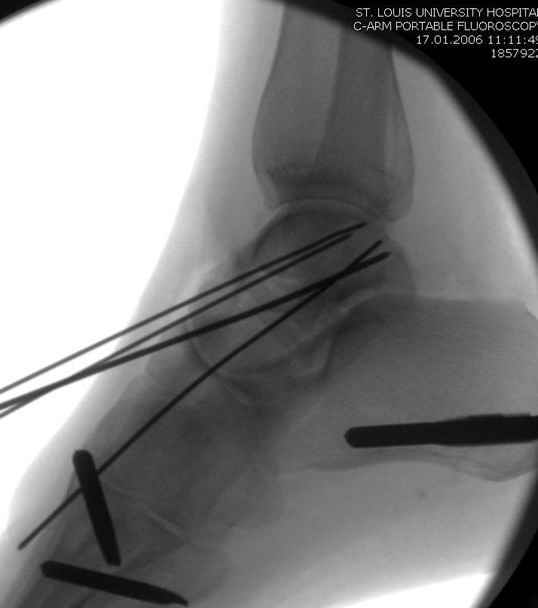

Вдогонку по поводу перелома таранной кости, больная 81, не страдает диабетом, перелом закрытый, в первый же день поступления ограничились временным наружным фиксатором (как на снимке).

Из-за отека на стопе тактика лечения у всех была

одинаковая: временная наружная фиксация до спадения отека, при изолированных переломах они выписывались домой и через дней 7 госпитализировались на оперативное лечение.

Примеры на снимке...